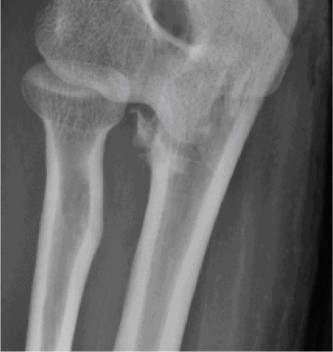

Plain Radiographs:

- Anteroposterior (AP) and lateral views of the elbow demonstrated a posteromedial dislocation of the ulna relative to the humerus.

- A significant fracture of the anteromedial coronoid process was clearly visible on the lateral view, displacing proximally.

- No obvious radial head fracture or olecranon fracture was identified on these initial views.

- The trochlea appeared to be displaced laterally relative to the coronoid fracture fragment.